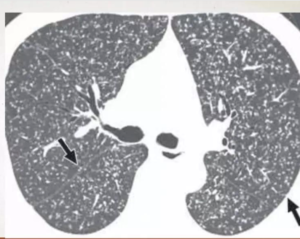

CECT show tuberculous nodes that show central areas of low attenuation suggestive of caseous necrosis and peripheral rim enhancement.

TUBERCULOUS NODE

• obtained at level of right middle lobar bronchus